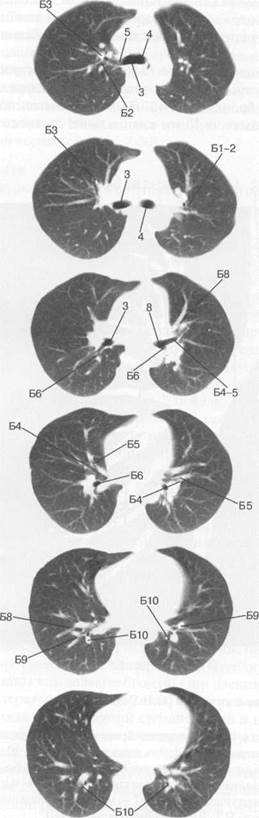

Анатомические изображения сегментов легких различных животных

Раздел: Другие животные